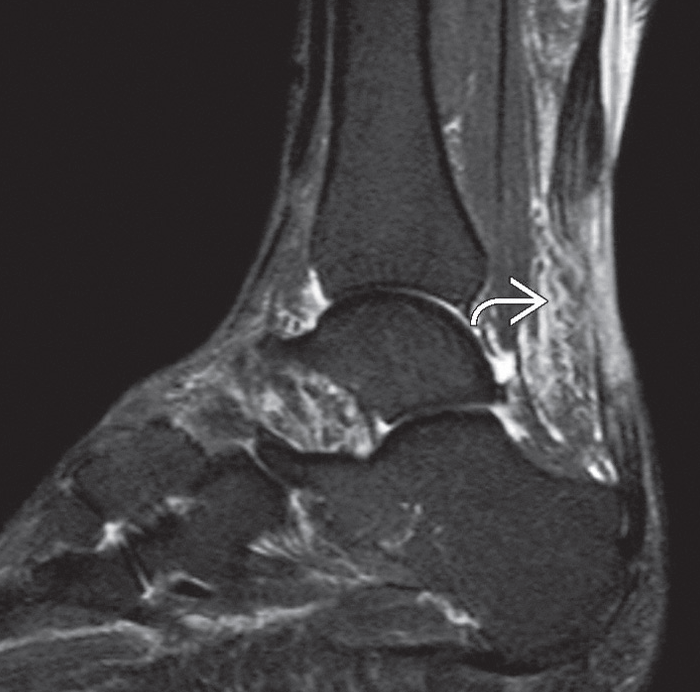

Muayene bulguları ile çoğu aşil tendon kopmalarının tanısı konulabilirken bazı olgularda manyetik rezonans görüntüleme ve ultrasondan da yararlanılır.

Aşil kopmasının A. Şematik görünümü, B. MR görüntüsü